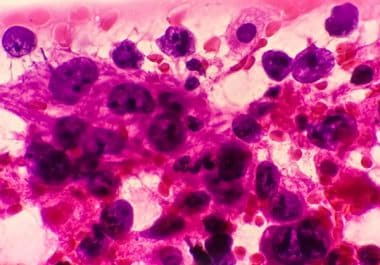

The FDA has approved amivantamab-vmjw, both alone and in combination with chemotherapy, for the treatment of certain non-small cell lung cancers. The U.S. Food and Drug Administration (FDA) has approved amivantamab-vmjw (Rybrevant), in combination...